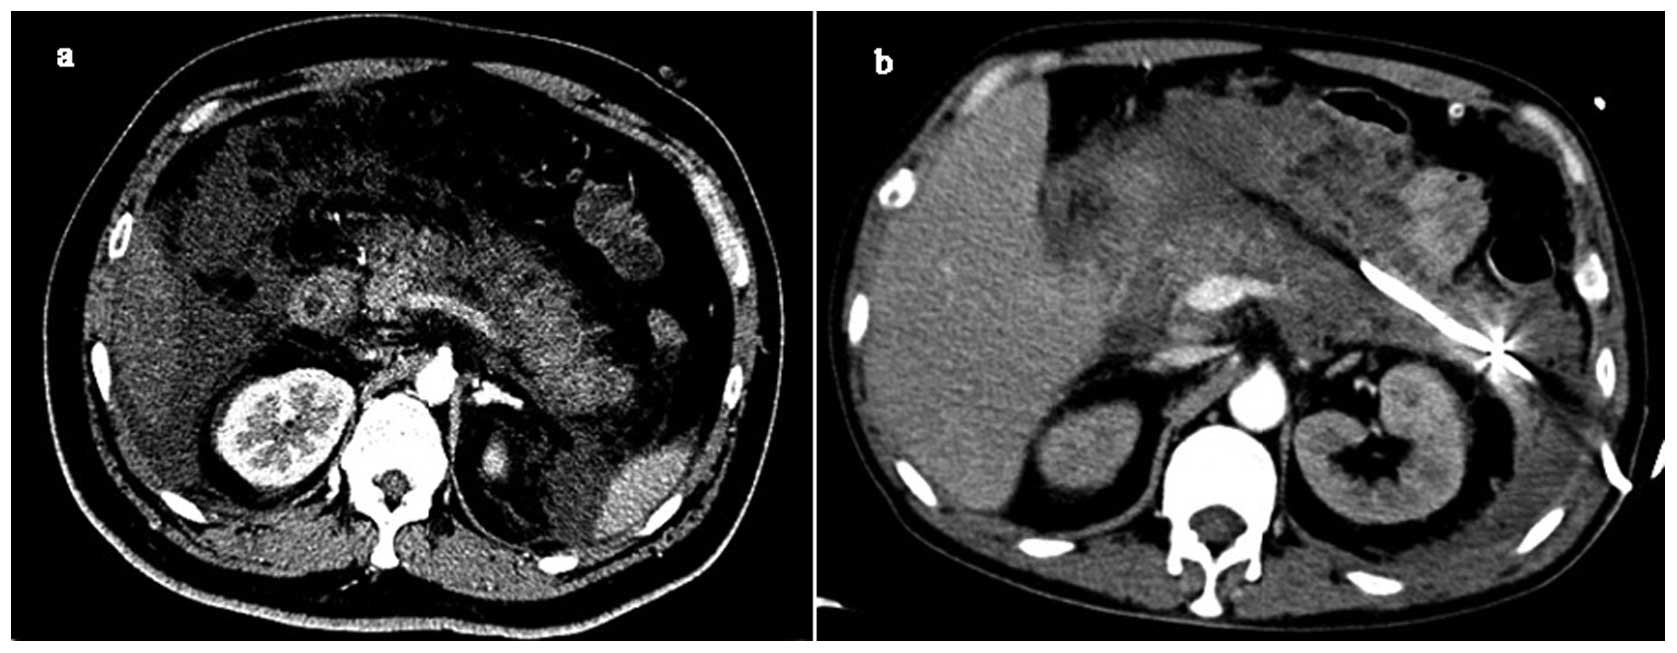

Для мочеполовой системы лучше мрт или кт - фото презентация